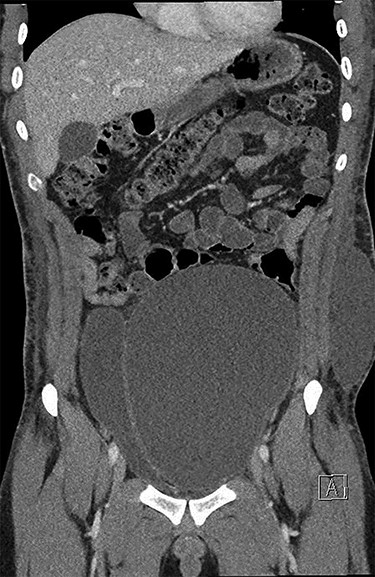

He underwent a computed tomography (CT) abdomen and pelvis, which demonstrated three subcutaneous cystic collections in the left flank, right flank and the left rectus abdominal muscle measuring 12.5 × 3.5 × 10.7, 5.9 × 1.2 × 7 and 1.2 × 1.8 × 2 cm. A large cystic intra-abdominal structure displaced the bladder to the right side and measured 18 × 14 x 7.6 cm (Figs 1 and 2).